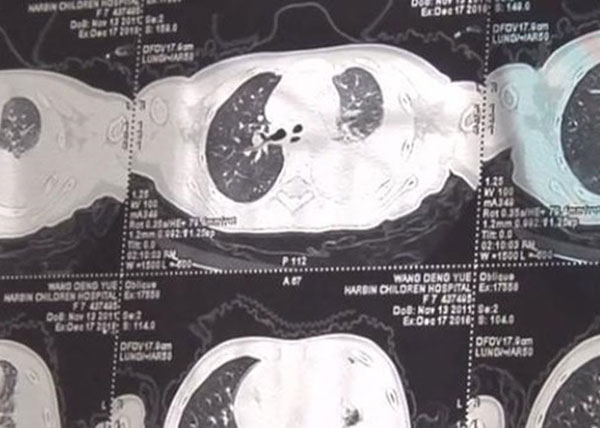

28/12/2018 22:25Con gái cảm sốt nhiều ngày, mẹ đưa đến bệnh viện thì phát hiện trong phổi có 600ml mủ và lời cảnh tỉnh về căn bệnh thường gặp ở trẻ

Vào ngày 26/12 vừa qua, truyền thông đưa tin một bé gái tên Nguyệt Nguyệt (tên đã được thay đổi) sống ở Cáp Nhĩ Tân, Hắc Long Giang, Trung Quốc vừa trải qua một cơn nguy kịch sau khi phát sốt do cảm lạnh. Mẹ của bé Nguyệt cho biết, vài ngày cuối tháng 11 thấy con bị cảm lạnh cô đã đi mua thuốc cho con uống. Tuy nhiên sau đó, bé Nguyệt bị sốt cao hơn, ngực bị đau. Thấy tình trạng con không ổn, đầu tháng 12 cô đã đưa Nguyệt đến bệnh viện địa phương để kiểm tra và phát hiện trong phổi trái của con gái có 600ml mủ. May mắn thay, các bác sĩ đã tiến hành phẫu thuật kịp thời, loại bỏ phần mủ trong phổi, nhờ vậy mà tình trạng của Nguyệt đang dần hồi phục.

Các bác sĩ cho biết: "Đứa bé được đưa đến bệnh viện trong tình trạng cả người lờ đờ và tinh thần không được minh mẫn. Lúc nhập viện, phổi của bé Nguyệt bị viêm khá nghiêm trọng. Nếu bố mẹ không đưa đến đây kịp lúc thì tình hình sẽ xấu đi, xuất hiện độc gây tổn hại đến não bộ. Vì vậy chúng tôi phải nhanh chóng làm phẫu thuật để loại bỏ mủ độc hại ở phổi trái đang xâm chiếm cơ thể cô bé".

Đại diện phía bác sĩ cũng cho biết thêm, bệnh viêm màng phổi mủ rất phổ biến ở trẻ em, nếu như bố mẹ không nhận biết được dấu hiệu thì tính mạng của bé sẽ gặp nguy hại. "Những đứa trẻ hiện nay khi bị viêm phổi đa số không được phát hiện kịp thời, dẫn đến tràn dịch màng phổi. Các bậc cha mẹ khi thấy con bị sốt hoặc cảm thì tốt nhất nên đến bác sĩ nhờ hỗ trợ, không nên cho con uống bất kỳ loại thuốc nào mà chưa được kê đơn", vị bác sĩ chia sẻ.